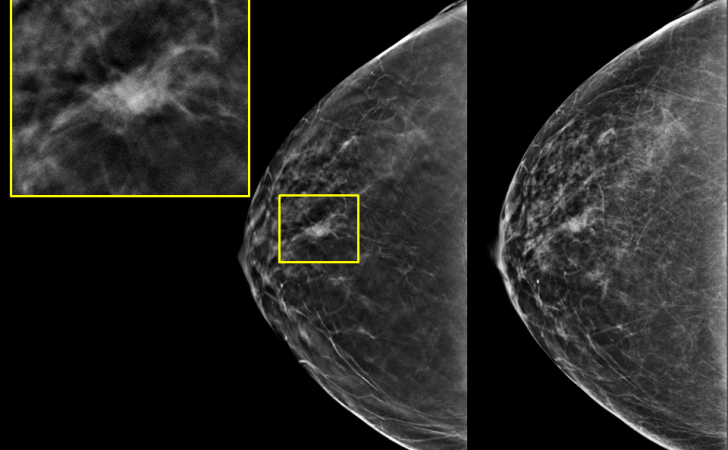

Esta tecnología avanzada permite obtener imágenes de la mama en una calidad superior – en relación con los sistemas anteriores – permitiendo analizar con mayor precisión y detectar lesiones en la mama con un diagnóstico más certero.

Con un mamógrafo digital directo es posible obtener una reconstrucción tridimensional de la mama, adicionalmente a la tradicional imagen 2D.

Esta tecnología permitirá aumentar la tasa de detección de cáncer mamario en etapas tempranas y disminuir los falsos positivos.